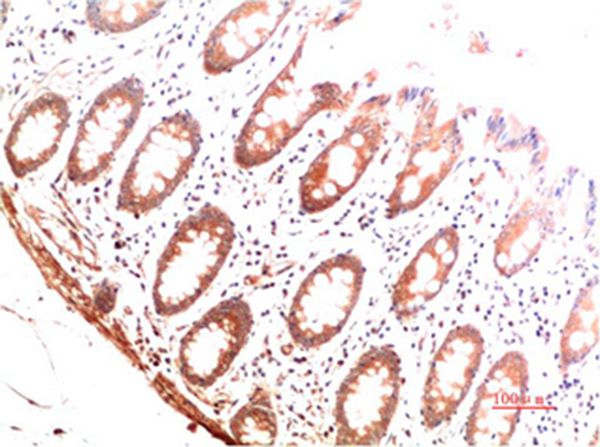

Immunohistochemical analysis of paraffin-embedded Human Colon Carcinoma Tissue using Collagen I Mouse mAb diluted at 1:200.